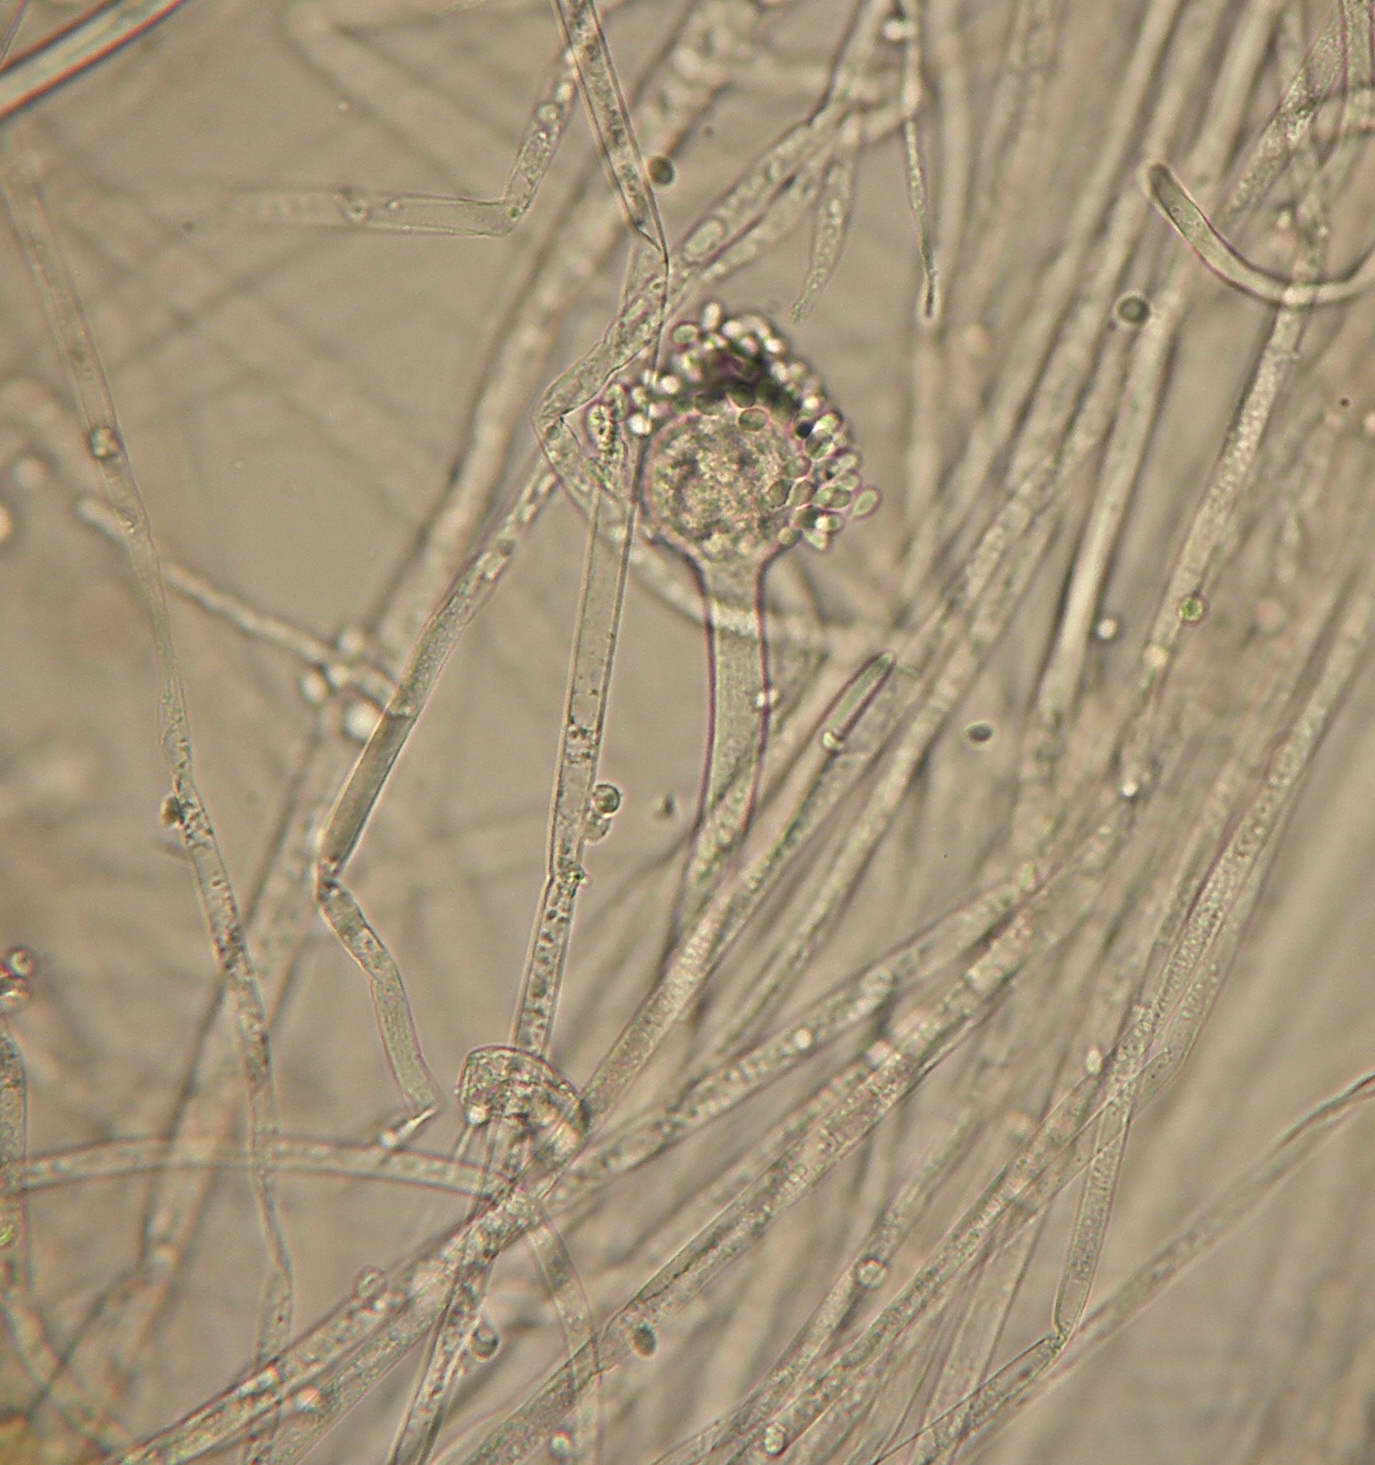

CUNNINGHAMELLA BERTHOLLETIAE (caso clinico nº2)